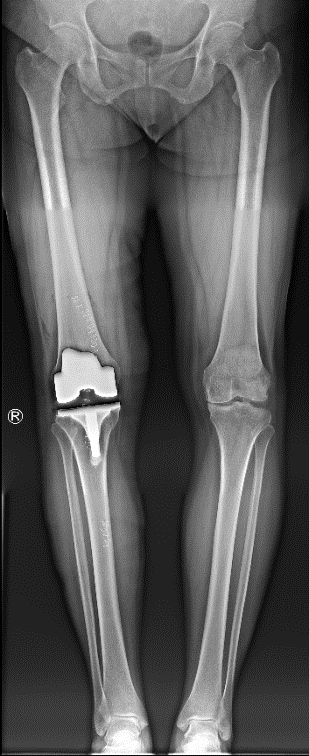

术后次日,患者杨阿姨即在医生指导下进行床旁行走训练,膝关节活动度逐步恢复。杨小海主任医师介绍,全膝关节置换术通过置换磨损的关节表面(类似“换保护套”),可显著改善因关节退变、软骨磨损导致的疼痛,患者术后很快即可恢复日常生活。本次所采用的骨科手术机器人辅助手术,通过三维影像精准规划截骨平面,术中实时调整截骨角度,相较于传统手术,可提升截骨的精准度与假体安放的精确性,缩短手术时间,减小创伤,降低术后并发症风险。杨阿姨术后复查X片显示膝关节假体位置良好,下肢力线合适。